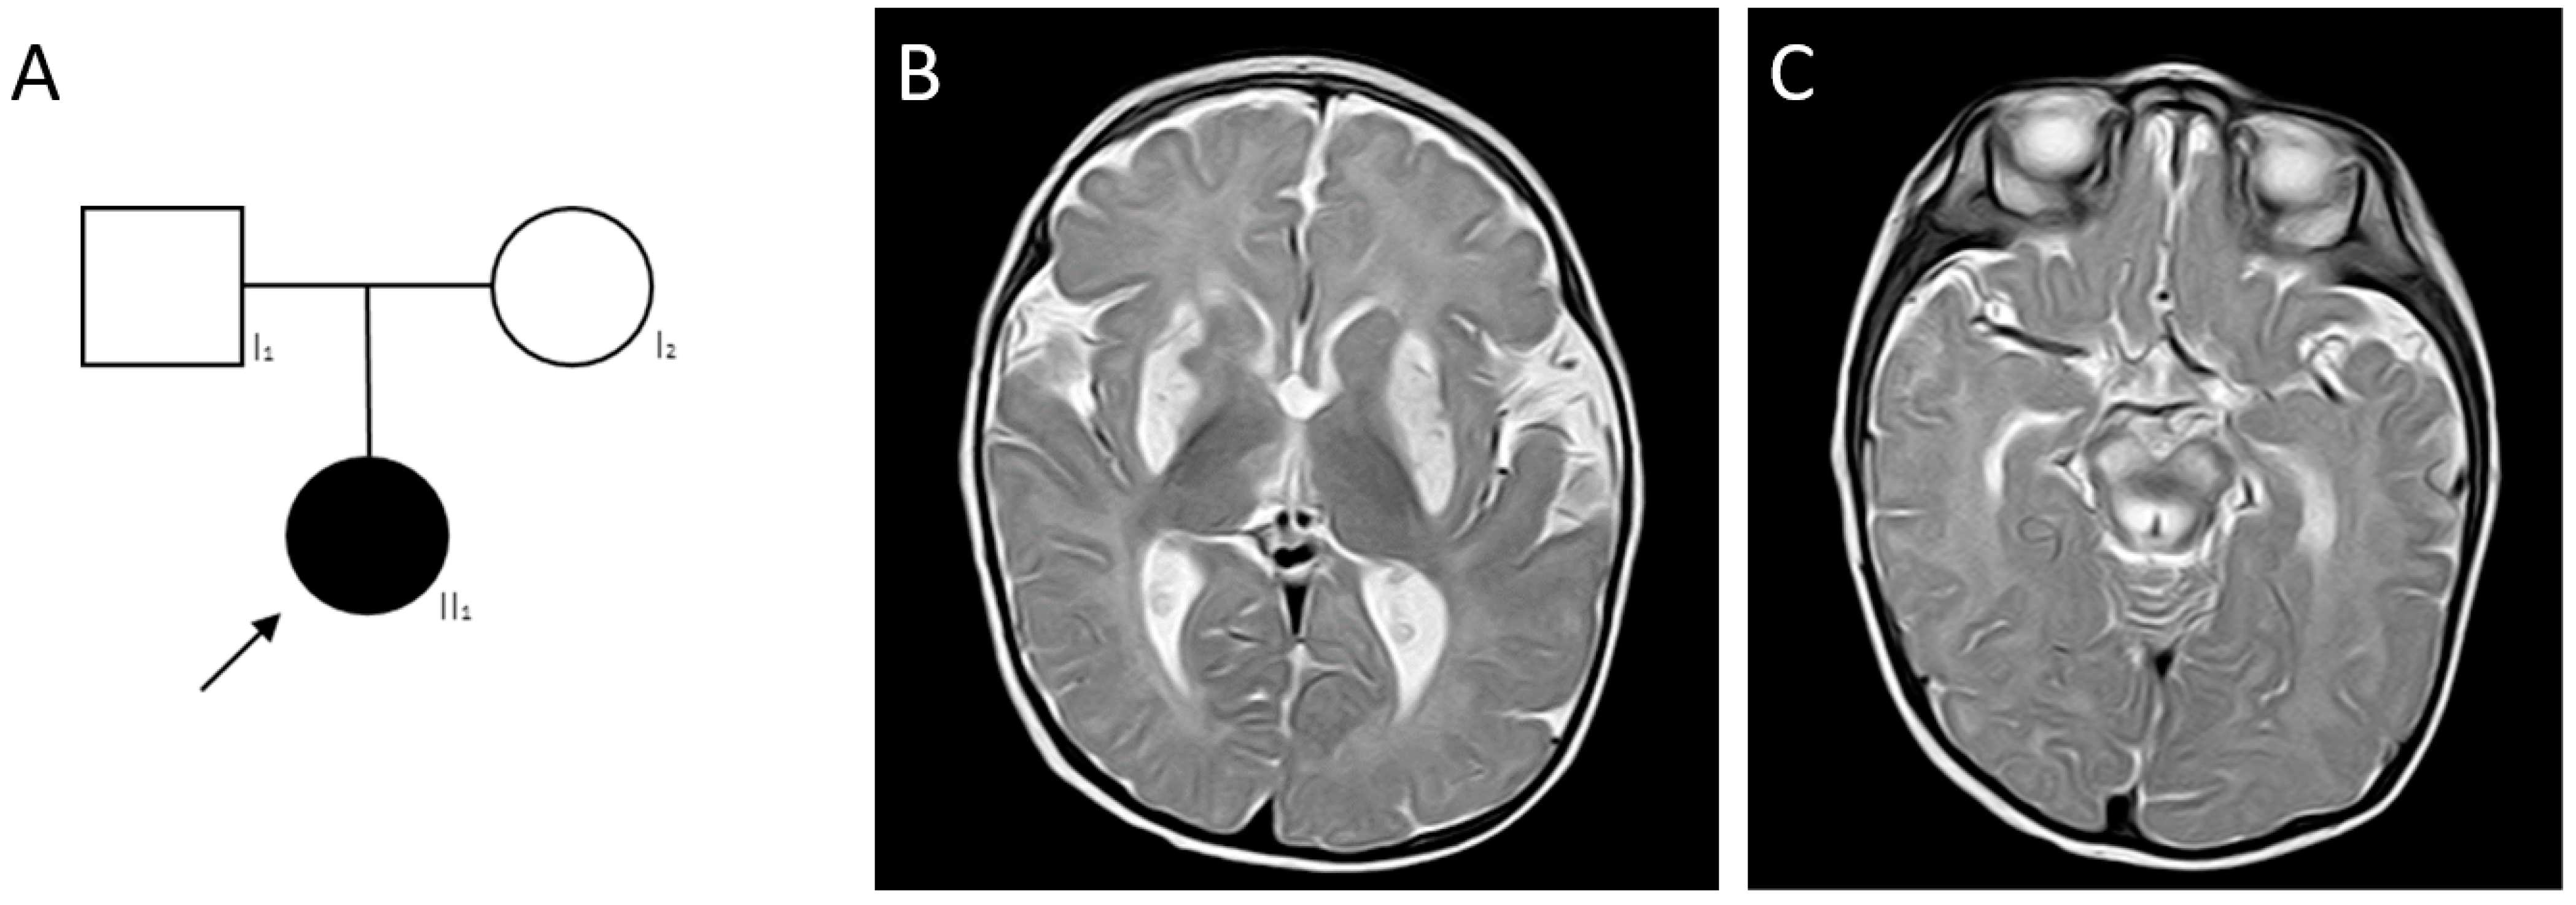

2.4. Clinical Cases